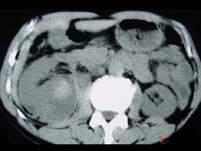

问题 男,25岁,右腰部疼痛伴血尿,有外伤史,CT扫描如图所示,应诊断为 ( )

选项 A、右肾梗死 B、右肾脓肿 C、右肾血管平滑肌瘤 D、右肾癌 E、右肾挫伤并包膜下血肿

答案 E